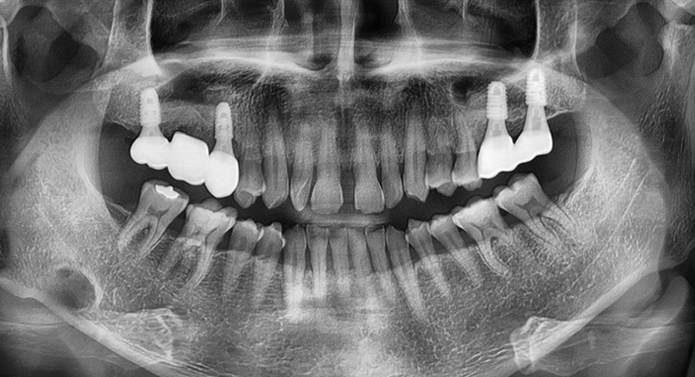

뼈가 부족한 경우에도 가능한 임플란트 솔루션 임플란트를 식립하려면 일정량 이상의 턱뼈가 필요합니다. 하지만 골다공증, 치주질환, 발치 후 방치 등으로 뼈가 부족하거나 얇아져 있는 경우엔 뼈이식이 필요합니다.

환자 개개인에 맞는 뼈이식 방식 선택 (동종골, 상악동 거상술, 자가골이식 등)

3D CT 분석으로 이식 범위·각도 사전 계획

흔들리는 임플란트를 새로 식립하고 필요에 따라 뼈이식을 진행합니다.

염증 치료 및 뼈이식 수술을 통한 잇몸뼈 보강합니다.

교합과 심미성을 고려하여 새로운 보철물 수복합니다.